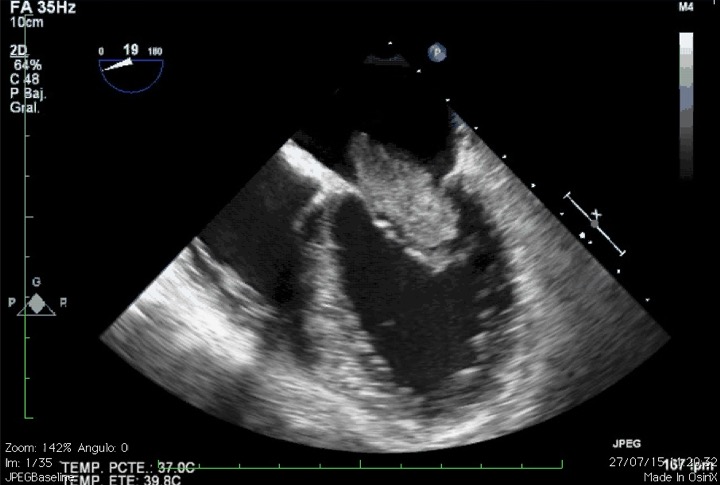

Tumor de aúrícula izquierda obstruyendo la válvula mitral.